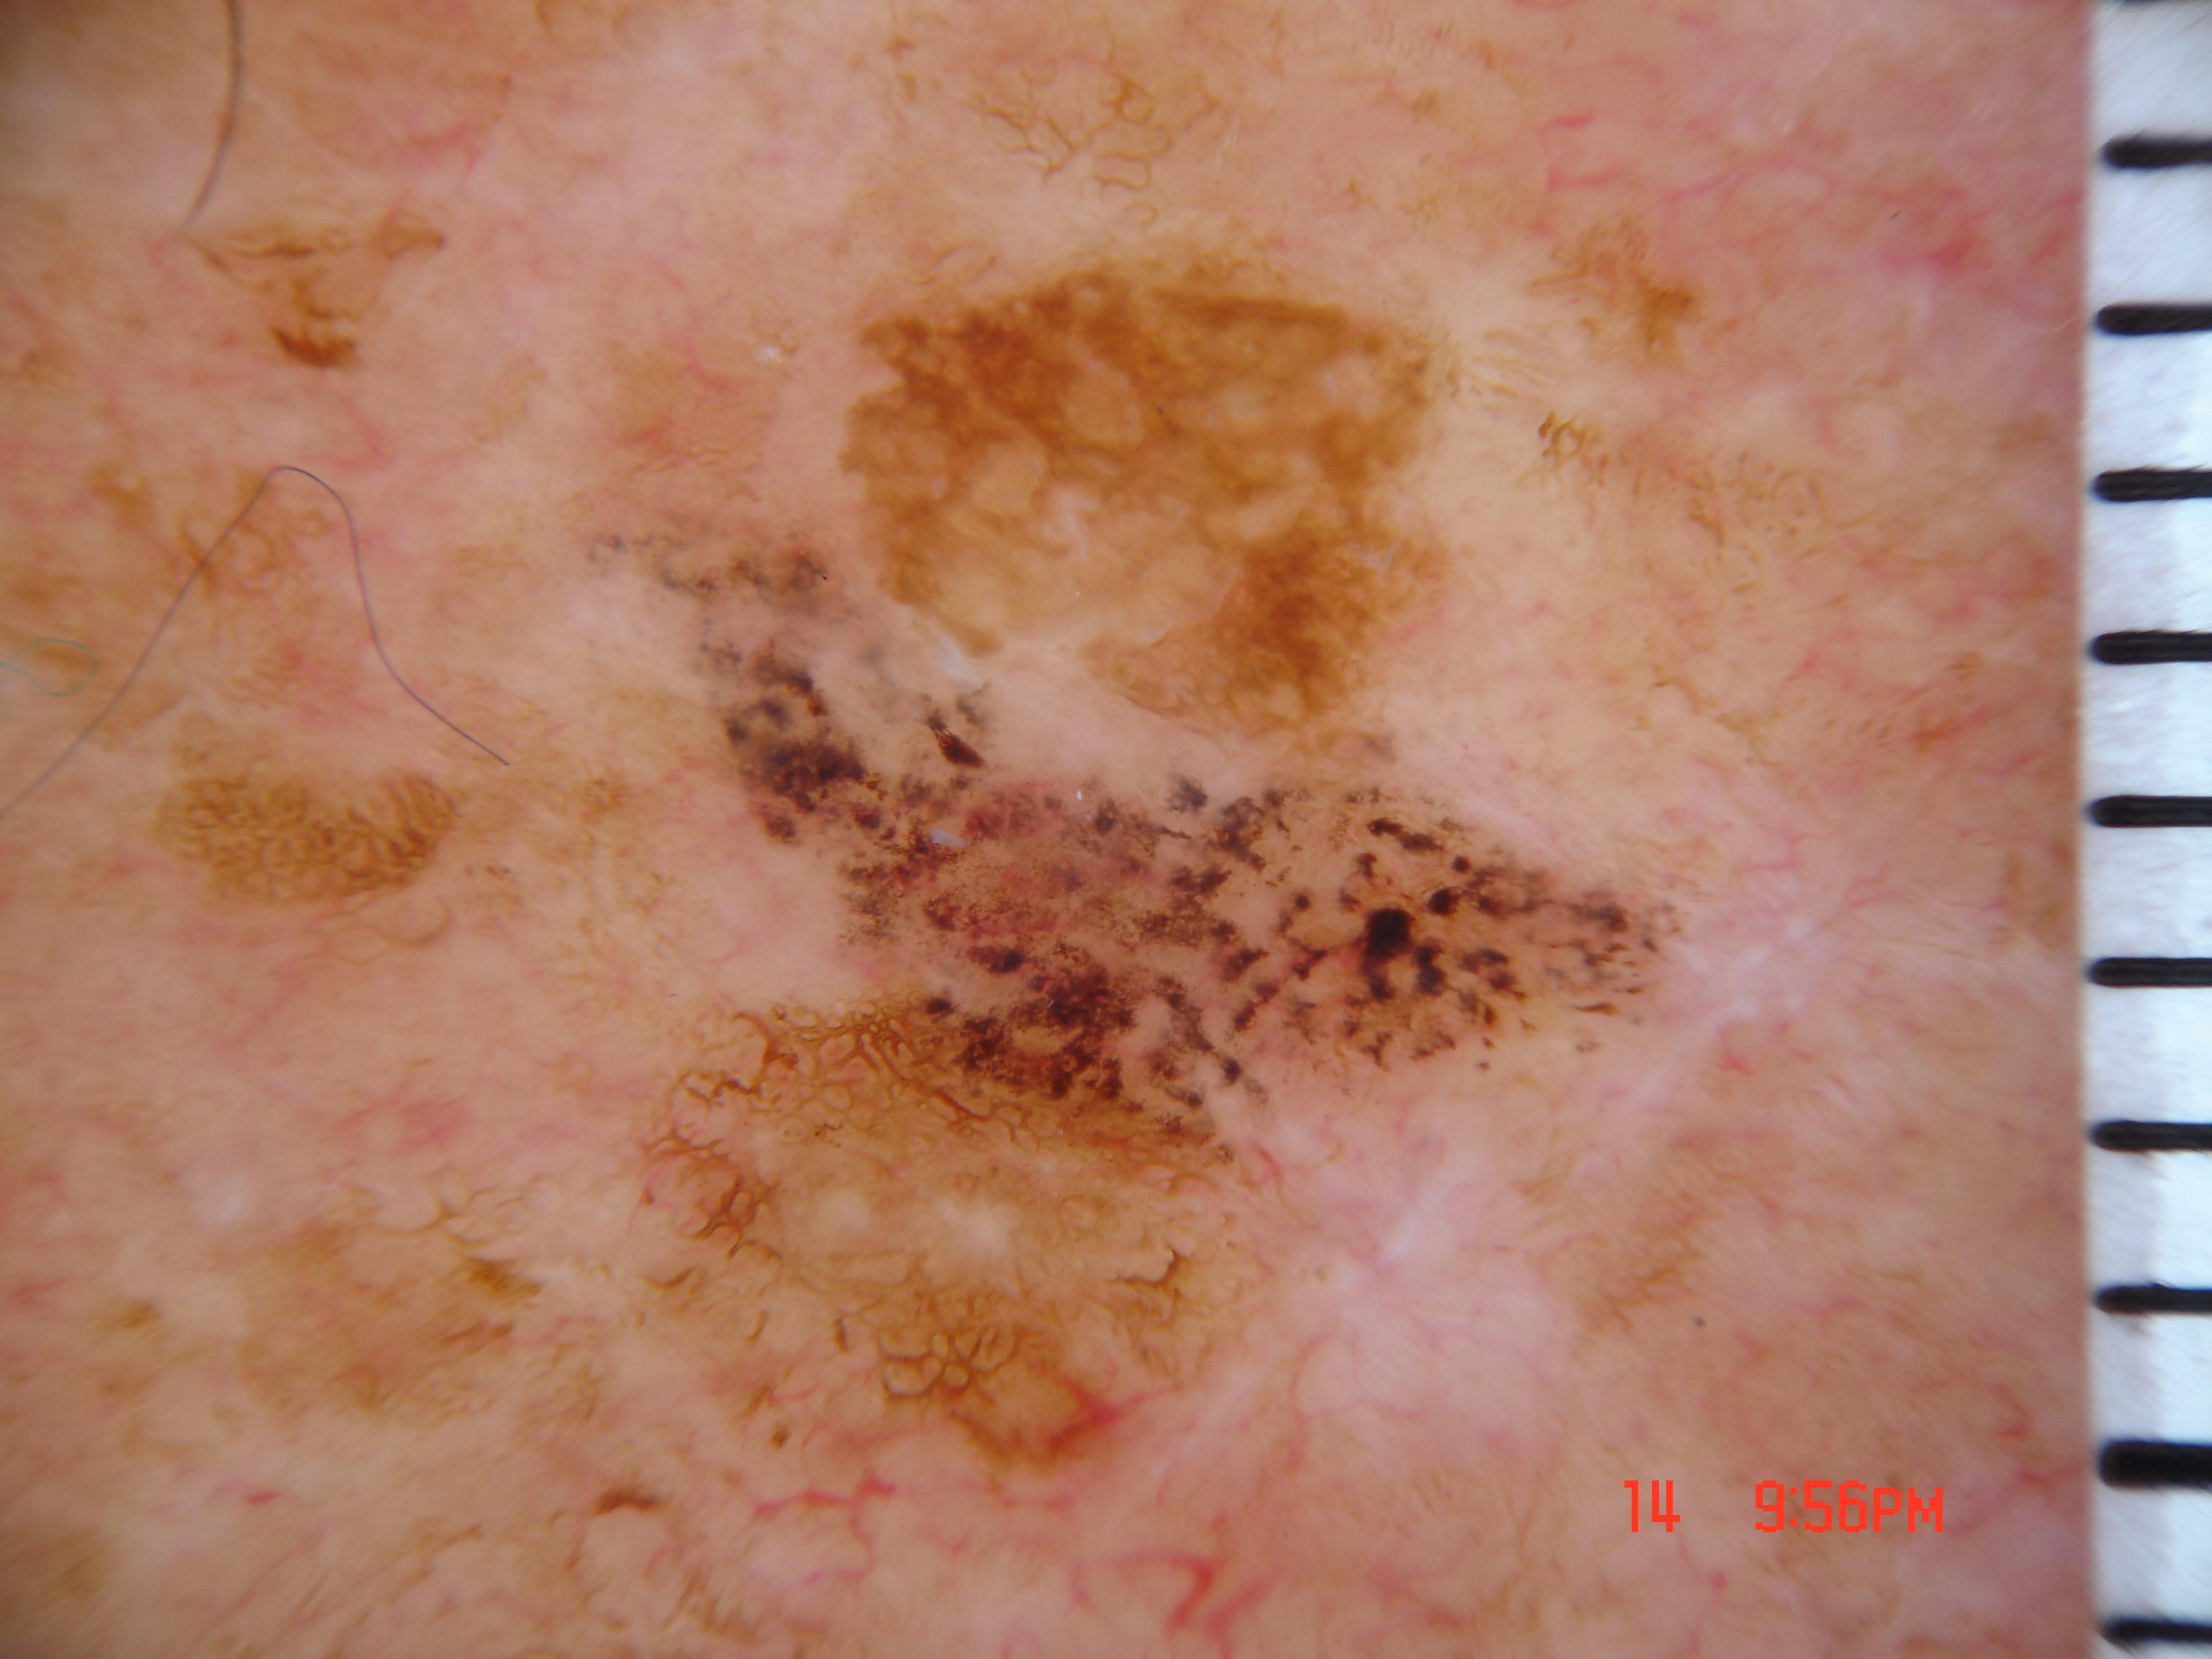

{

"age_approx": 65,

"anatom_site_general": "head/neck",

"concomitant_biopsy": true,

"dermoscopic_type": "non-contact polarized",

"diagnosis_1": "Malignant",

"diagnosis_2": "Malignant epidermal proliferations",

"diagnosis_3": "Squamous cell carcinoma in situ",

"diagnosis_confirm_type": "histopathology",

"family_hx_mm": false,

"image_type": "dermoscopic",

"melanocytic": false,

"patient_id": "IP_0406746",

"personal_hx_mm": false,

"sex": "male"

}